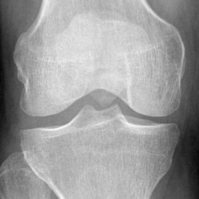

Refer to caption

(a) A standard knee plain radiograph

(b) An identified knee joint

Figure 3: A standard knee plain radiograph from the database and an identified knee joint highlighted in a red box 3(a). An identified knee joint 3(b).